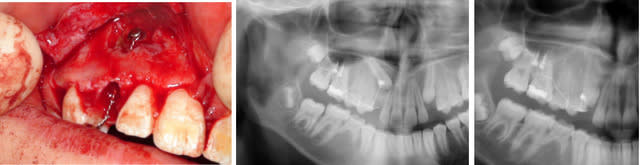

jeune fille pour une désinclusion de 23, 10 ans sur la carte vitale, dentition en avance pour son age

je suis content car l'intervention est banale, mais je n'en avais jamais trouvé autant, + 2 autres dans l'aspiration

sur la pano j'étais parti pour 2 surnuméraires

Sinon c'est un odontome composé ton truc = tumeur odontogène

Sans doute hormis les deux surnumerairaires tout était dans un sac, mais comme, je ne m'y attendais pas je ne peux pas dire s'il était fermé ou ouvert.

sur la photo 2 on distingue les 2 germes l'un au dessus de l'autre (eh non pxav je n'y arrive tjrs pas pour les photos)

trajet , "excision" sinon cela saigne un peu trop, dégagement de la couronne a minima,collage pose de la chainette en traction, régularisation des cretes, sutures